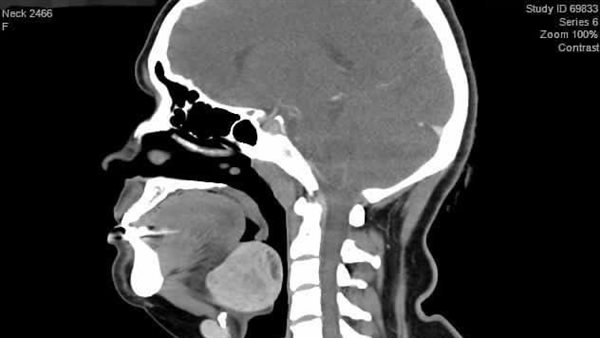

وأوضح الدكتور أحمد غنيم، عميد كلية الطب ورئيس مجلس إدارة المستشفيات الجامعية بطنطا، أن المريضة كانت تعاني من عيب خلقى نادر وهو وجود الغدة الدرقية بالجزء الخلفى من اللسان مما كان يسبب لها صعوبة فى التنفس والبلع والاختناق أثناء النوم.

وأضاف عميد طب طنطا، أن تخدير المريضة كان يمثل تحدياً نظرًا لوجود الغده الذى يماثل حجم البرتقاله فى مجرى التنفس، لكن نجح فريق التخدير بتركيب أنبوب تنفس للمريضه بمنظار القصبة الهوائية بمهاره فائقه دون أن تشعر المريضة بأى ألم، بعدها قام الفريق الجراحى بإستئصال الغده من الفم باستخدام المنظار الجراحى